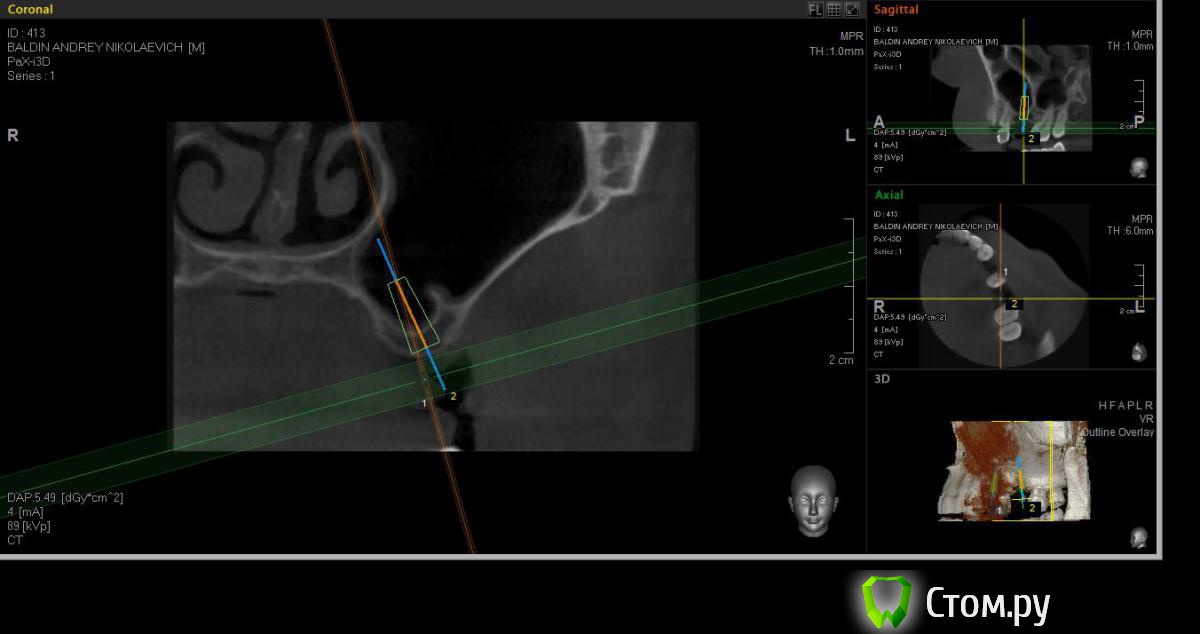

faity Опубликовано 25 апреля, 2014 Автор Поделиться Опубликовано 25 апреля, 2014 а вот это не помешает? Ссылка на комментарий

syrovovec Опубликовано 25 апреля, 2014 Поделиться Опубликовано 25 апреля, 2014 Не помешает, делайте окно медиальнее Ссылка на комментарий

red_butler Опубликовано 25 апреля, 2014 Поделиться Опубликовано 25 апреля, 2014 септа даже поможет снизить расход графта Ссылка на комментарий

faity Опубликовано 25 апреля, 2014 Автор Поделиться Опубликовано 25 апреля, 2014 септа даже поможет снизить расход графтая честно говоря очкую шнейдара порвать при такой анатомии 1 Ссылка на комментарий

kriokov Опубликовано 25 апреля, 2014 Поделиться Опубликовано 25 апреля, 2014 я честно говоря очкую шнейдара порвать при такой анатомииоткрытый делайте, нормальная анатомия, септа там не помеха. Сами посмотрите внимательно на кт-- кортикалка в синусе хорошо оформлена, мембрана не тонкая - риск что нарветесь на спайки в обл дна минимальный 3 Ссылка на комментарий

faity Опубликовано 27 апреля, 2014 Автор Поделиться Опубликовано 27 апреля, 2014 исправил срезы, перепланировал ход.оба импланта по 11 мм, открытый синус, если открою перегородку септы- расширюсь дистальнее и откушу её, если нет, то в её пределах графт(примерно 1,5гр)+стружка(примерно 2-3 гр)+prp(флакон), ФДМ.критика приветствуется Ссылка на комментарий

Bier Опубликовано 27 апреля, 2014 Поделиться Опубликовано 27 апреля, 2014 В данном случае септу не нужно трогать вообще. Считайте, что в этом месте пазуха заканчивется. 3 Ссылка на комментарий